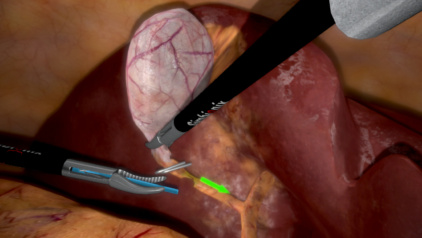

Train in a Life-Like Environment

This module allows the trainee to perform the steps of the intra-operative cholangiography procedure in a life-like environment – from the delicate side cut through the complicated insertion of the catheter into the cystic duct, to the injection of contrast agents. Educational aids include video-based content, interactive visual step-by-step guidance and objective performance metrics.

- To demonstrate control of the cystic duct with ideally positioned clips

- To perform proper incision in the cystic duct while avoiding unnecessary complications

- To practice safe and accurate catheter insertion into the cystic duct